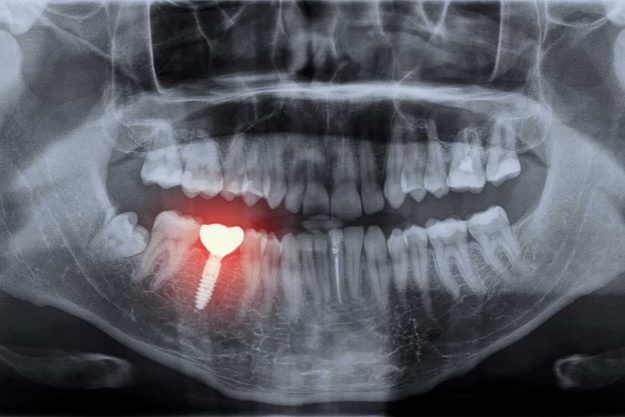

How Do Dental Implants Work?

When you lose a tooth, you may have a moment of panic before wondering what your options are. You can opt for a crown or bridge or, if you lose more than one tooth, you may choose a partial plate with artificial teeth. However, there’s another option that mimics the look and feel of your…